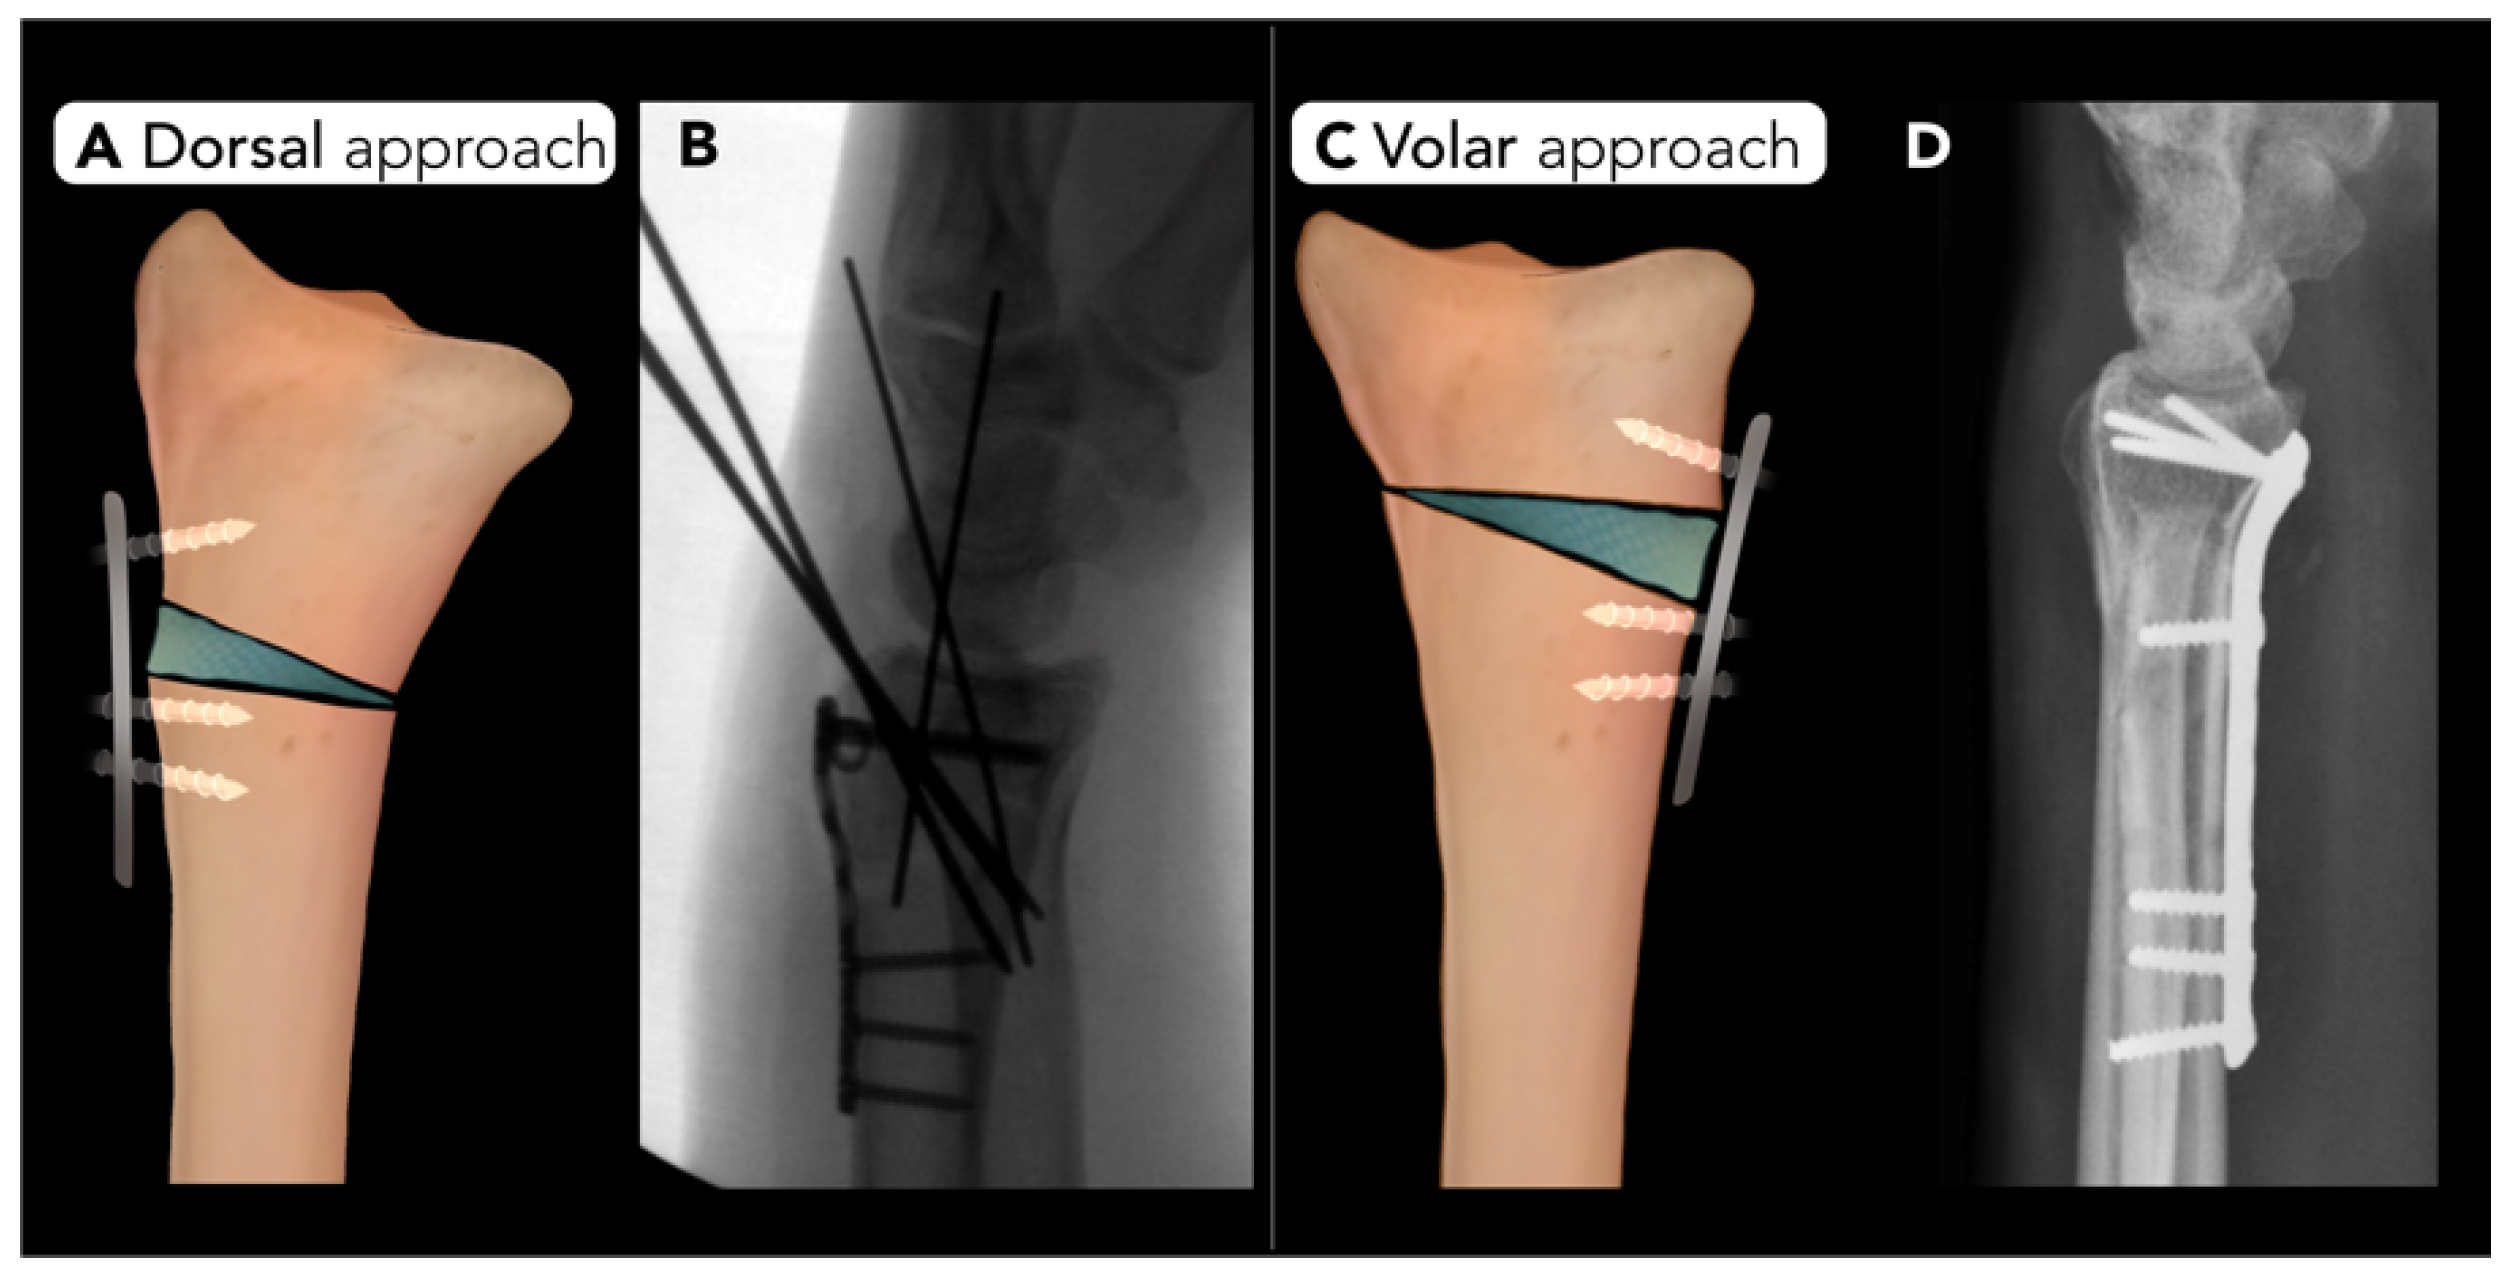

2.2.3. Distal Radius Corrective Osteotomy